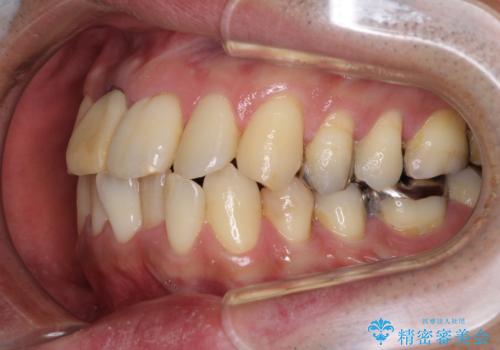

隠れている前歯 インビザライン矯正治療と前歯のセラミック治療

- 隠れるほどに内側に転位しいてる前歯を気にして来院された患者様です。

仕事柄海外出張が多いとのことで、インビザラインにて矯正治療を行うこととしました。

矯正治療後は、前歯や下顎の奥歯など、むし歯治療途中の歯をオールセラミッククラウンにて補綴治療を行うこととしました。

内側に転位していた前歯は、矯正治療では治しきることができませんでしたが、幸いにもオールセラミッククラウンに置き換える予定であったため、希望通りの仕上がりとなりました。